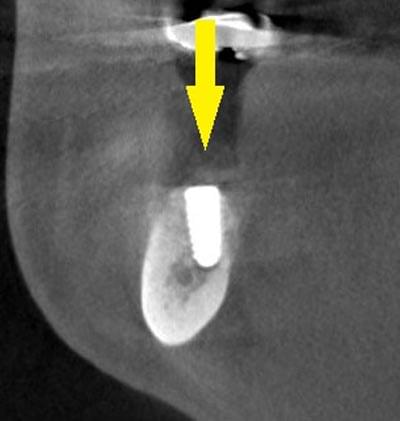

移植した骨が周囲の骨と、結合したのを待ち、6か月後に、インプラント埋入手術を行いました。下の写真が、インプラント埋入後のCT画像で、黄色矢印に示すように、インプラントが2本埋入できました。

インプラント埋入後の、別な方向からみたCT画像です。神経の通る管にややギリギリでしたが、神経は傷つけずに、インプラントが埋入できました。この後、4か月ほどで、咬む歯の部分、上部構造を完成させました。